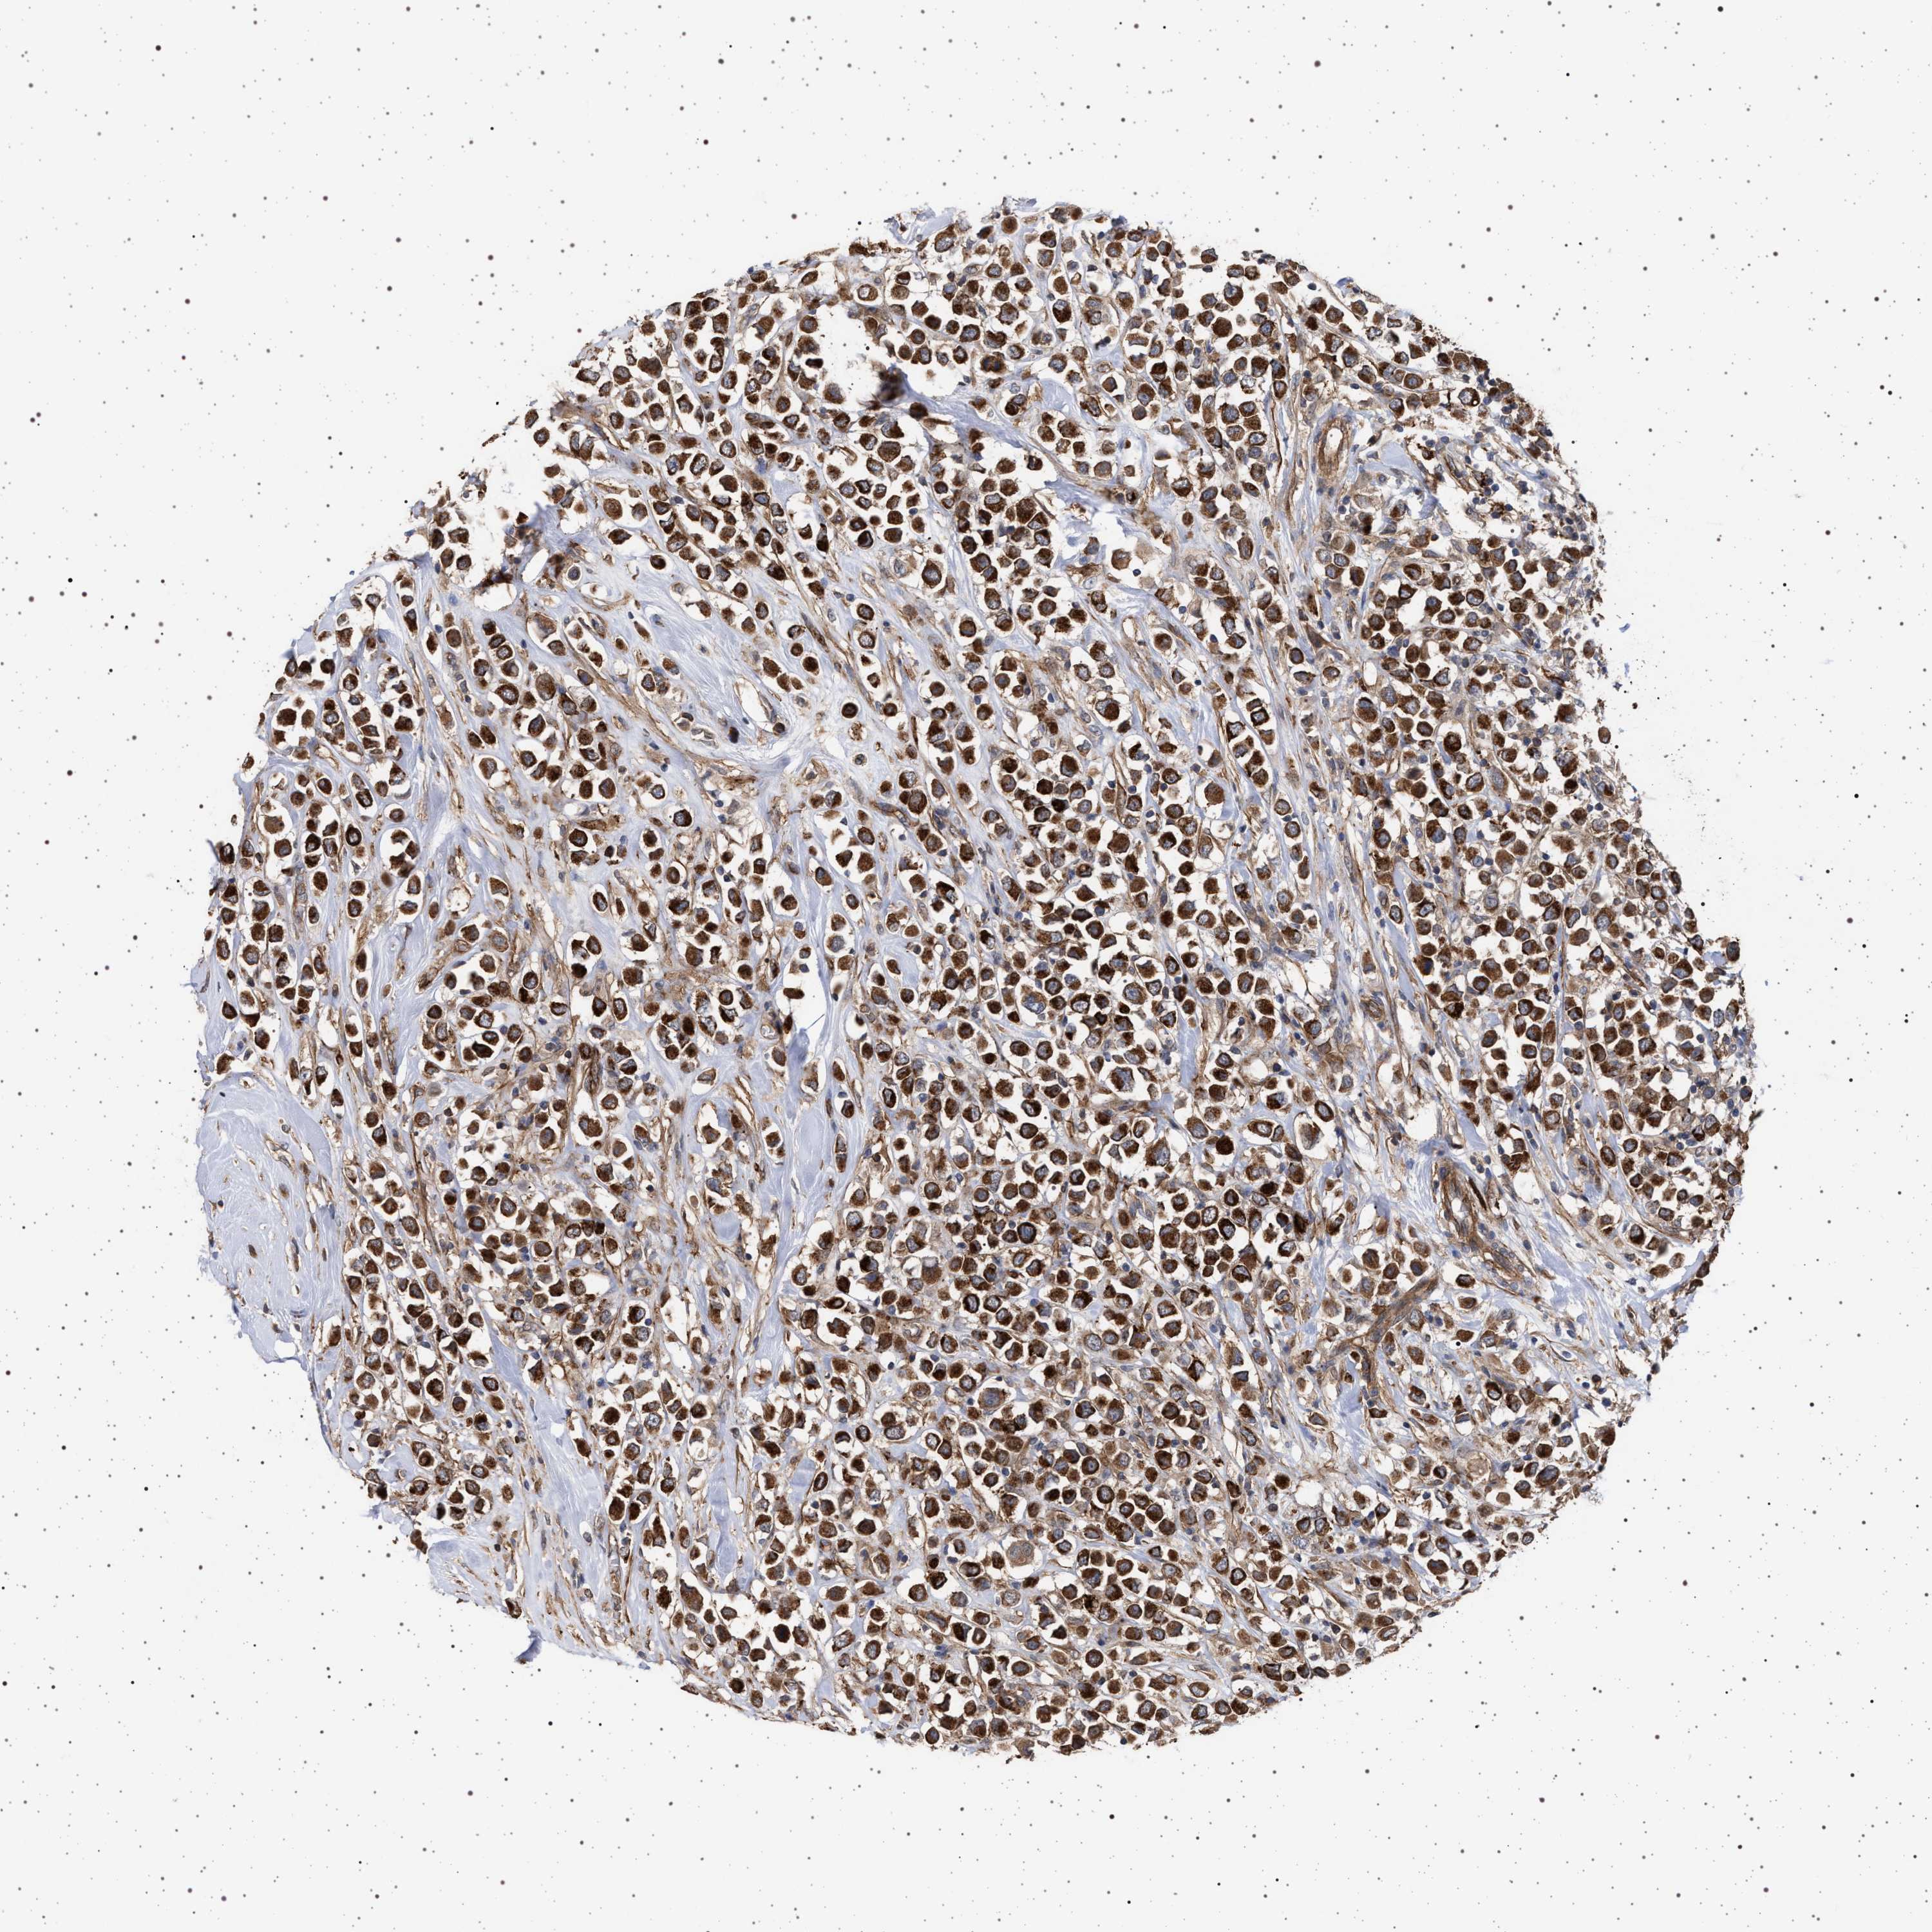

CANCER BREAST CANCER Show tissue menu

BRCA TCGA BRCA VALIDATION PROTEIN EXPRESSION